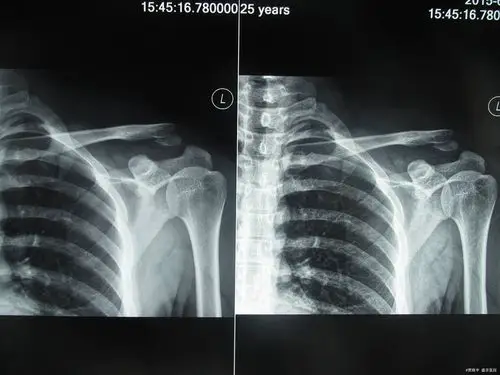

锁骨右侧肩峰骨折.静养时错位,已16天.

左锁骨肩峰端骨折

肩部骨折会有局限性疼痛,可导致肢体功能完全丧失,并发症有休克